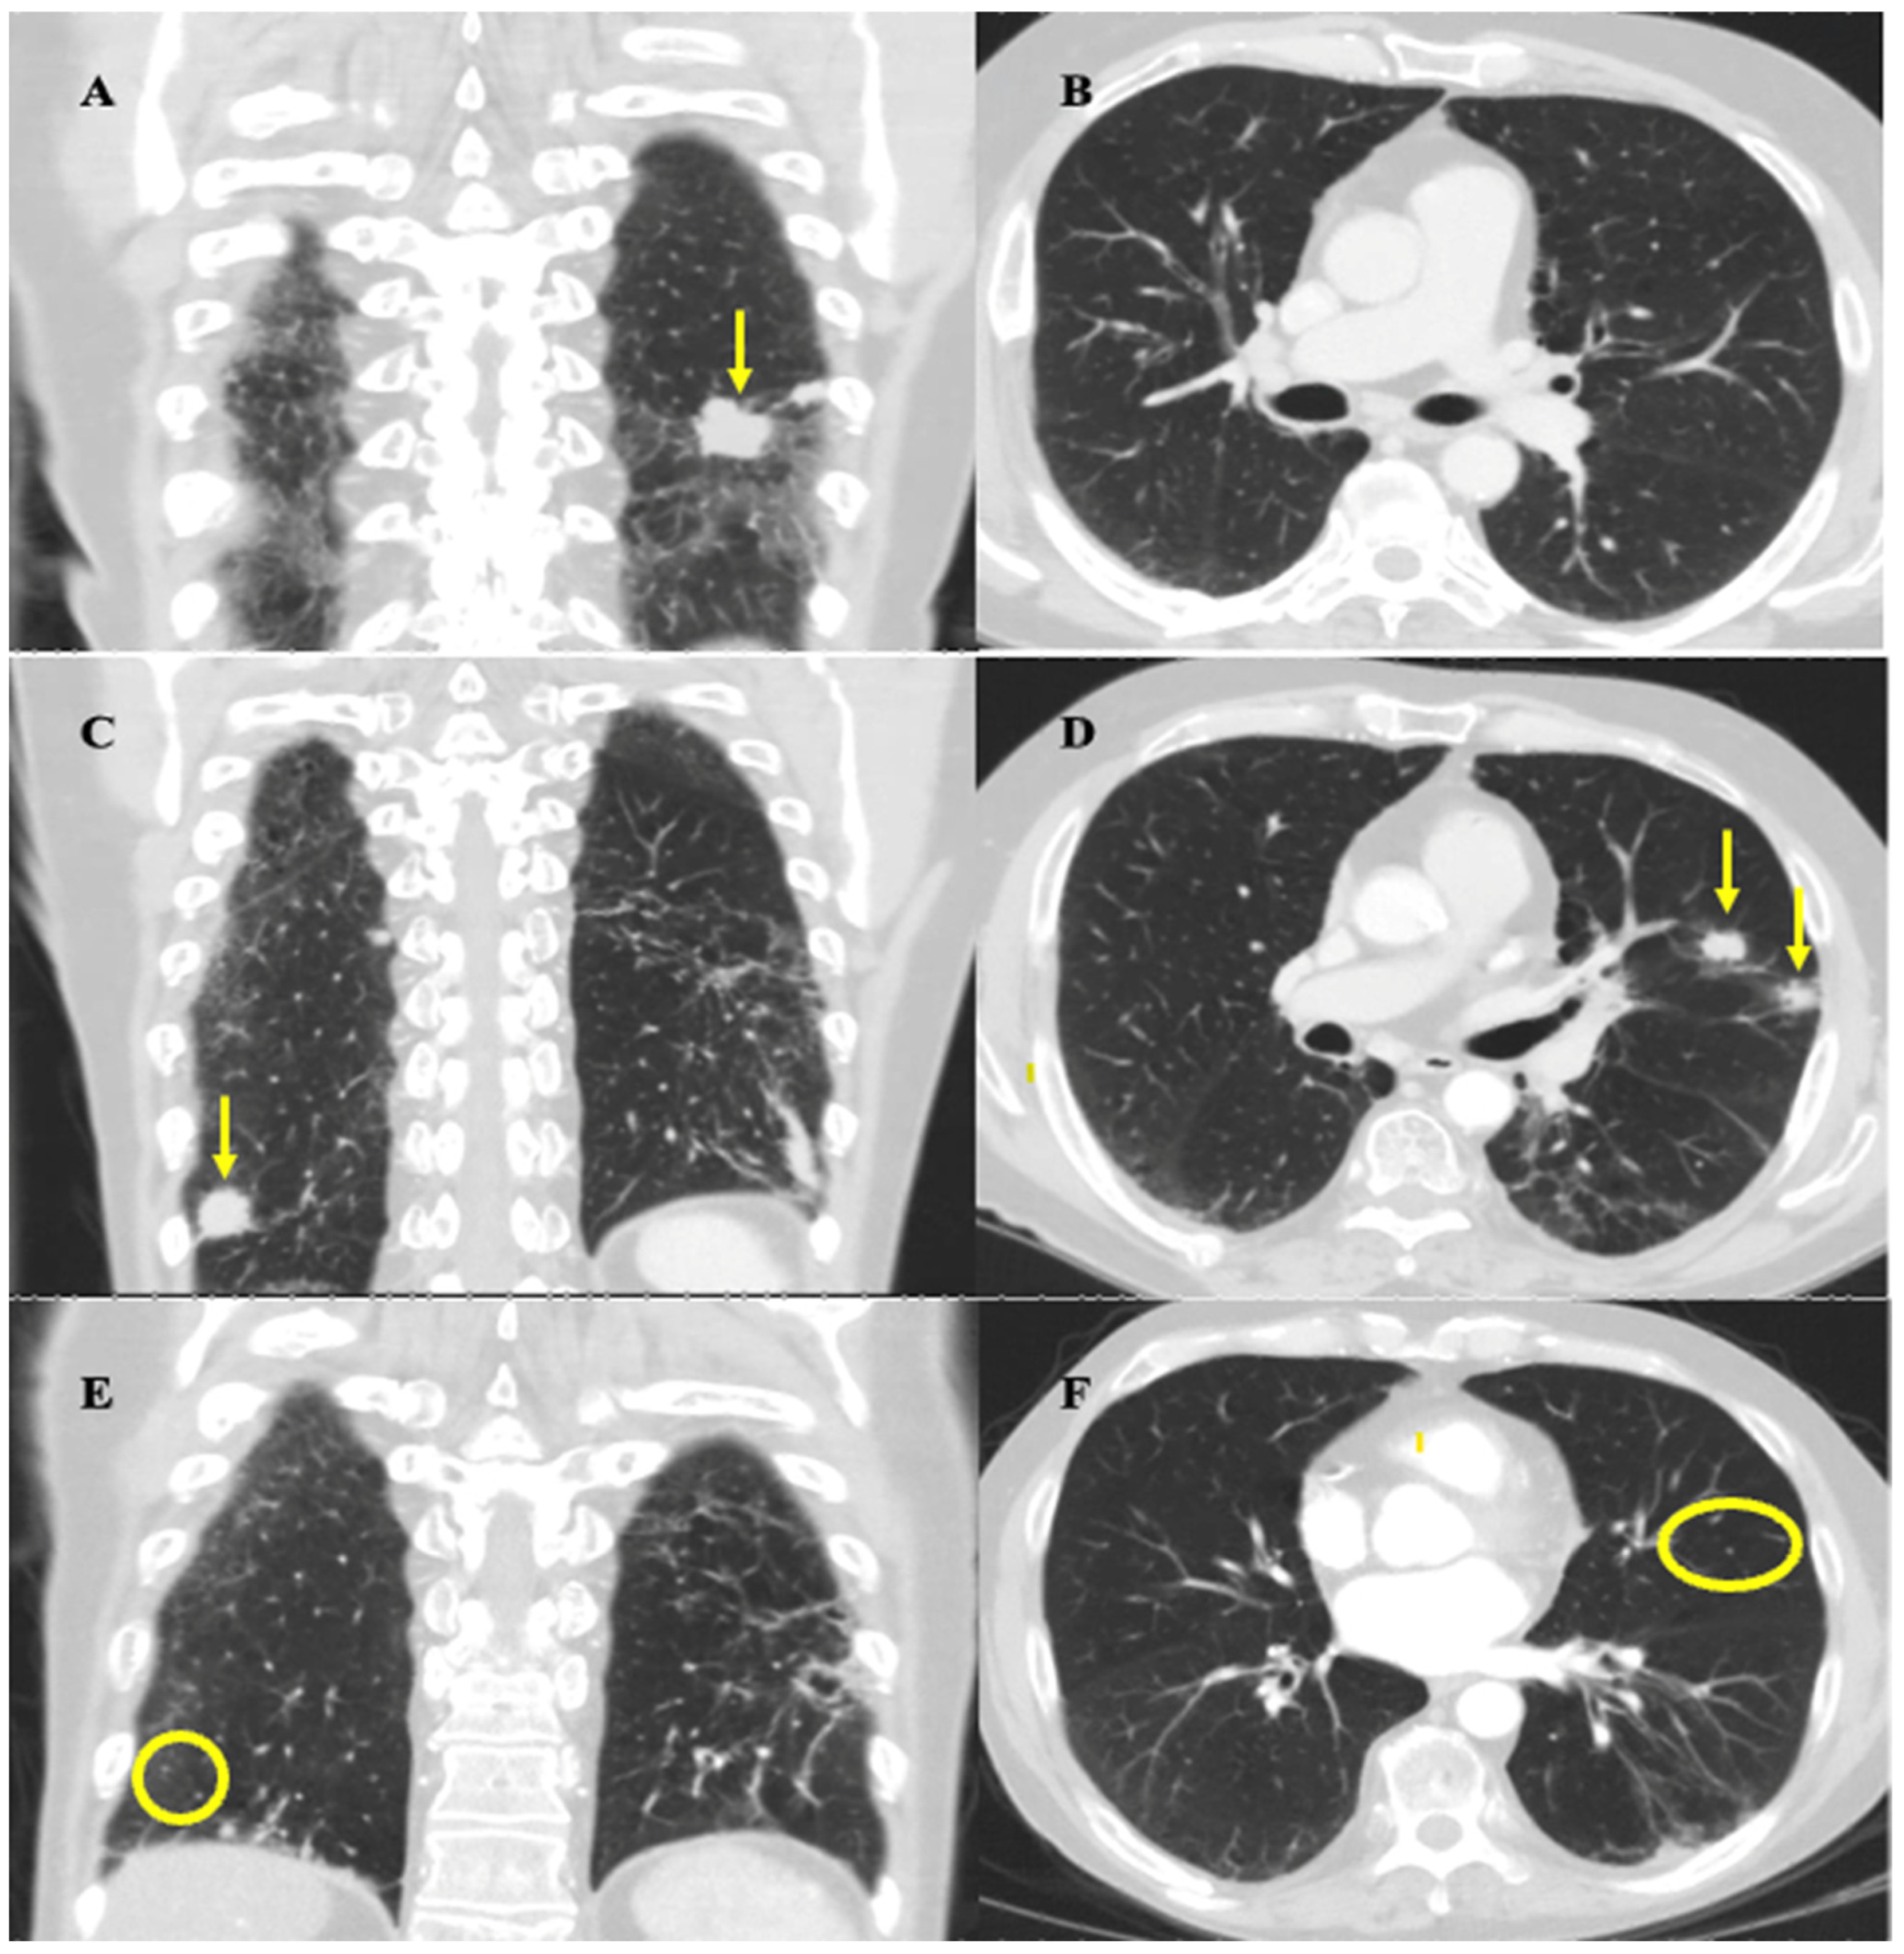

Figure 2.

Coronal and axial mid-lung CT thorax images highlighting important stages of disease progression and response to therapy. Images were obtained at approximately the same slices for each time point. (A,B) February 2020 imaging after induction chemotherapy and radiation showing treatment response. (A) Arrow highlights reduction in size of largest left lung nodule from 3.4 × 2.8 cm to 2.7 cm × 1.6 cm. (B) No evidence of metastatic nodules in mid-lung zones of left and right lung zones at the level of the hilum. (C,D) September 2020 imaging showing progression of disease. (C) Coronal view shows resolution of largest left lung nodule but appearance of a new right lung nodule near the costophrenic angle, indicated by the arrow, measuring 1.9 cm. (D) Axial view shows appearance of two new metastatic nodules in left upper lobe, indicated by the arrows, each measuring approximately 1.4–1.5 cm in size. (E,F) March 2021 imaging post rechallenge with chemotherapy and atezolizumab showing near-complete resolution of disease. There is resolution of the nodules seen on the September 2020 scan (circles highlight locations of previously seen, now resolved, lesions). Residual scarring was also observed.

The follow-up CT thorax scan on February 2020 showed a partial response to this initial regimen, as most of the metastatic pulmonary nodules decreased in size, including the largest nodule, which decreased from 3.4 × 2.8 cm to 2.7 cm × 1.6 cm, and there was no evidence of new metastatic disease (Figure 2A,B). After a multidisciplinary case conference discussion verifying safety, the patient underwent radiation therapy to the left lower lobe pleural-based lesion, left-sided hilar and mediastinal lymph nodes, and left neck from March to April 2020 (30 Gy in 10 fractions to each site). This decision was made with the intent to prolong survival and was informed based on the results of the CREST trial [6]. Maintenance atezolizumab was held during radiotherapy to decrease the risk of compounding side effects. Radiation was well tolerated overall, with his main side effect being mild odynophagia which did not impact nutrition. The patient declined to undergo prophylactic cranial irradiation (PCI) and opted for an MRI surveillance approach instead.

In July 2020, standard CT surveillance showed a mixed response to treatment. A CT thorax/abdomen scan showed a decrease in size of the largest nodule at the left lung base (now 1.3 × 2.0 cm) and right hilar and subcarinal lymph nodes, but an increase in size of the pre-existing nodules, along with the appearance of new suspicious nodules. The decision from our institution’s thoracic tumor board meeting in August 2020 concluded that these findings were more in keeping with true progression as opposed to pseudoprogression. In Sept 2020, a CT thorax/abdomen scan demonstrated further disease progression by highlighting the size increase of the metastatic nodules uncovered in the July 2020 scan (Figure 2C,D). The patient developed mild shortness of breath, but otherwise felt well, and functional status remained unchanged. This progression prompted the patient to undergo rechallenge with induction chemotherapy along with continued immunotherapy. The decision to rechallenge with platinum chemotherapy was made as he experienced a platinum-free interval of greater than 6 months (approximately 9 months) before relapse, and was therefore platinum chemo-sensitive [7]. Atezolizumab was continued because, given the mixed response, it could not be concluded that this medication had definitively failed. Given these factors, and his high tolerability for atezolizumab up to this point, rechallenge with the induction chemotherapy regimen and subsequent continued immunotherapy was deemed the best approach for this patient.

He completed six cycles of carboplatin (225 mg IV, day 1), etoposide (143 mg IV, day 1–3), and atezolizumab (1200 mg IV, day 1) every 21 days from Oct 2020 to Jan 2021, with the duration chosen to maximize the effectiveness of the rechallenge and given his ongoing tolerance. Chemotherapy was initially dose-reduced by 25% as in his last cycle of the first round, and a further dose reduction to 35% of carboplatin and etoposide on cycle three was required due to the development of anemia (carboplatin 195 mg IV, etoposide 124 mg IV). He experienced mild fatigue throughout the rechallenge, and additional symptoms of dysgeusia and loss of appetite at the last cycle of treatment. A CT head/neck scan performed in December 2020 showed resolution of the left-sided neck mass and associated lymphadenopathy. A CT thorax/abdomen scan performed in March 2021 demonstrated complete resolution or reduction in size of most metastatic pulmonary nodules, and the resolution of mediastinal lymphadenopathy (Figure 2E,F). These results demonstrated a positive response to rechallenge. Maintenance atezolizumab was subsequently restarted with the plan to continue surveillance imaging every 3–4 months.